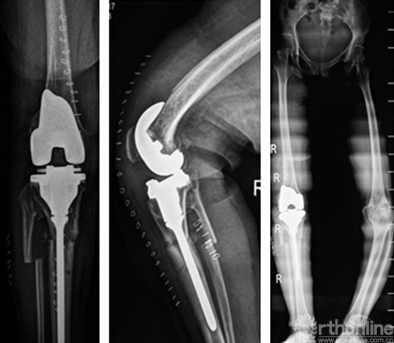

该患者术后下肢畸形得到较好的矫正、获得良好的下肢力线及关节活动度,术后6个月随访,KSS膝关节评分85,而ROM为0°-100°。X光片未见假体松动迹象。

术后影像

术中取膝正中纵行切口,髌旁内侧人路,首先与股骨侧模型比对后去除软骨,运用股骨侧导板及3D四合一截骨板依次完成股骨截骨;然后进行胫骨侧模型对比和标记,对后去除软骨,运用胫骨侧导板完成胫骨平台截骨;3D模型对比找出固定点固定导板模块行胫骨矫形截骨;进行矫形后,通过模块固定断端,测试伸屈间隙,3D模块固定进行假体安装。采用爱康ACCK假体:股骨侧:A3 S2#;胫骨平台:ACCK 1#(定制处理),胫骨平台加长杆:生物固定型非偏置、直径8mm、80mm长,假体采用水泥固定,延长杆采用生物固定。